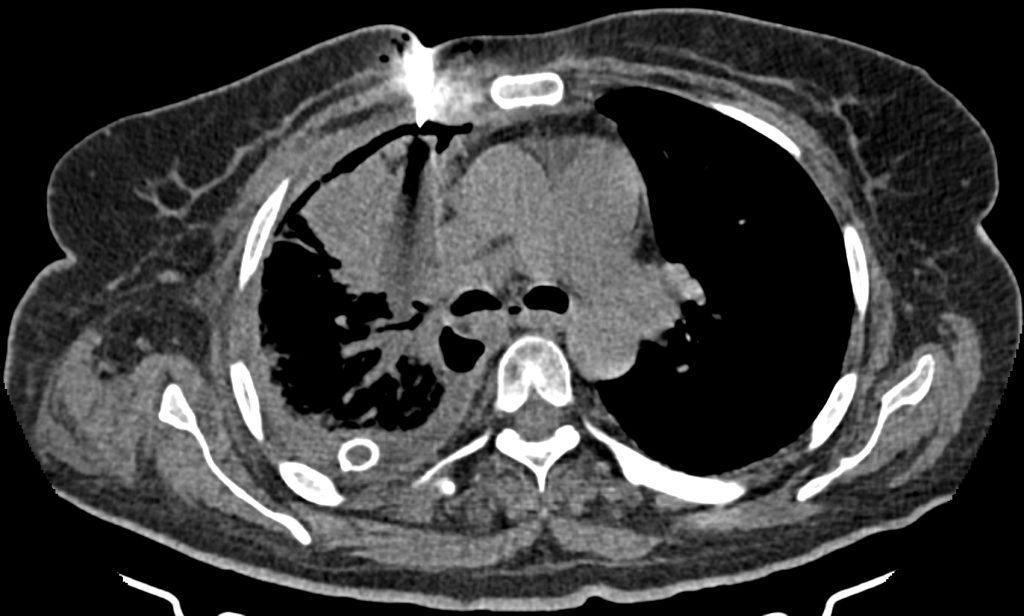

تحت هدايت سي تي اسکن سه نمونه CNB از توده سگمان آنتريور لوب فوقاني راست تهيه شد .

تصاوير پيوست قرارگيري سوزن در توده را نشان مي دهد .